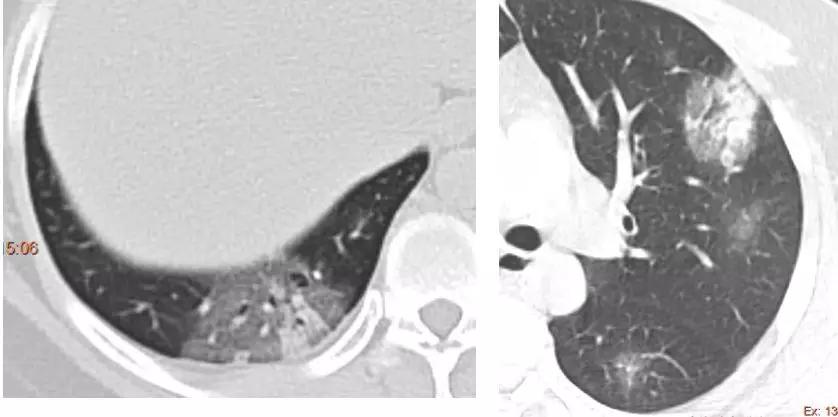

病例 1 男性,78 岁,发热 2 天

CT 示:两肺近胸膜下多发磨玻璃影;内见支气管充气征